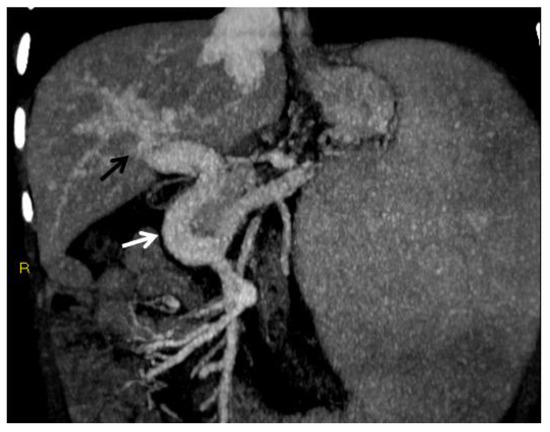

MR is less operator dependent than CDUS, though more so than CT. Similar to CT, MR readily depicts typical findings of PVT including the extent of portal vein occlusion, potential occlusion of the superior mesenteric and splenic veins, and the extent of portosystemic collaterals and secondary changes in the liver (Figure 7). In the evaluation of portal cavernoma cholangiopathy, magnetic resonance cholangiopancreatography (MRCP) better depicts the changes in the biliary system than CT—avoiding ionizing radiation and providing high-quality images of the bile ducts and vessels—and replaces the diagnostic role of percutaneous transhepatic cholangiography and ERCP, reducing the risks of bleeding and acute pancreatitis associated with the latter [49]. One typical finding is the ‘‘wavy’’ appearance of the biliary ducts related to extrinsic compression by the collateral vessels, which was described in 87.5% of patients in one small retrospective study [46,47]. Other typical MR findings of the biliary system include areas of stenosis and dilatation, angulation of the common bile duct at the level of the superior pancreatic head (with an angle of ≤145 degrees considered significant) [61], and wall thickening of the gallbladder and bile ducts. Wall thickening may be related to intramural varices, as previously described, or ischemic fibrosis [46] (Figure 2). Epicholedochal collateral vessels may appear as punctate foci of intramural enhancement within the ducts on postcontrast MR images [61]. Bile duct and gallbladder stones are also well depicted on MRCP images. MR can also show other potential complications, including cholangitis and hepatic abscesses [46].

Figure 7.

MR of a 50-year-old male with chronic portal vein thrombosis and portal hypertension. (a) Axial T1-weighted contrast-enhanced MR image shows low signal intensity within the right branch of the portal vein (arrow). Splenomegaly is a typical hallmark of portal hypertension (black arrow). (b) Axial T2-weighted MR image shows that portal vein thrombosis appears of increased signal intensity (arrow).